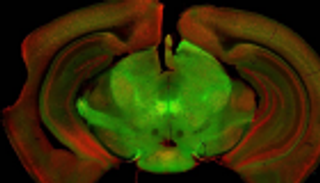

خلال الدراسة، أراد الفريق البحثي رؤية ما حدث عصبياً عند غياب الجين "PCDH19" في أسماك "الزرد"، وباستخدام مجهر ذي قدرة عالية تمكّنوا من مراقبة التغيّرات على المستوى الخلوي، إذ رصدوا اختلافات واضحة بين التطوّر الجنيني في "الزرد" العادي والآخر الجنيني الذي غاب عنه الجين.

وقال جيمس جونتس، أستاذ مشارك في علم الأعصاب والباحث الرئيسي بالدراسة، في تقرير نشره الموقع الإلكتروني لجامعة أوهايو: "رأينا كثيراً من الترابطات بين الخلايا العصبية في أسماك الزرد التي غاب عنها الجين، وبدا الأمر كأننا أمام عدد كبير جداً من الخلايا جرى دمجها في شبكة من الخلايا العصبية".